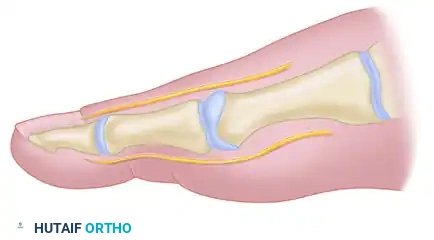

BIOMECHANICS OF THE SESAMOID APPARATUS

A core component of the modified McBride procedure is the lateral release, which addresses the deforming forces acting on the first MTP joint. In a hallux valgus deformity, the metatarsal head drifts medially, slipping off the sesamoid apparatus. The sesamoids, tethered by the transverse metatarsal ligament, remain in their anatomical position relative to the second metatarsal, appearing radiographically as though they have subluxated laterally.

Correction is significantly improved by the release of the adductor hallucis and the lateral head of the flexor hallucis brevis (FHB). In severe, non-reducible cases, excision of the fibular (lateral) sesamoid may be considered.

Biomechanical advantages of fibular sesamoidectomy:

* Releases the adductor hallucis and lateral head of the FHB, markedly reducing the valgus moment at the first MTP joint.

* Prevents the pull of the fibular sesamoid on the flexor hallucis longus (FHL) through its tendon sheath and pulley system, neutralizing another potent valgus-producing force.